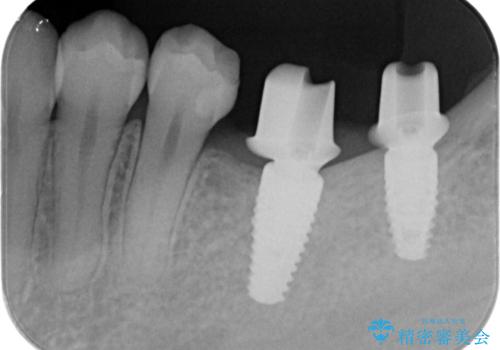

- 奥歯が二本欠損しており、その奥に親知らずが残っていました。

インプラントの一時手術と親知らずの抜歯を同時にしています。

- 70.2万円費用は治療当時の料金となります